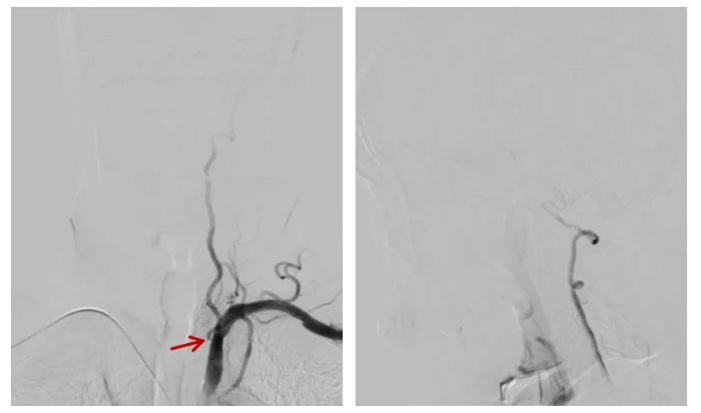

微导丝通过狭窄段,球囊扩张:将微导丝小心穿过狭窄段,用小球囊对狭窄处进行扩张,扩张后残余狭窄约 60%。

支架植入:沿导丝送入椎动脉药物支架至狭窄段,采用「半释放」技术,在导引导管辅助下逐步打开支架,确保位置精准。